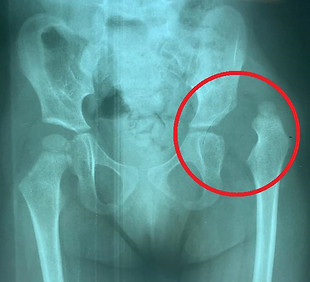

Algumas das Doenças Tratadas: